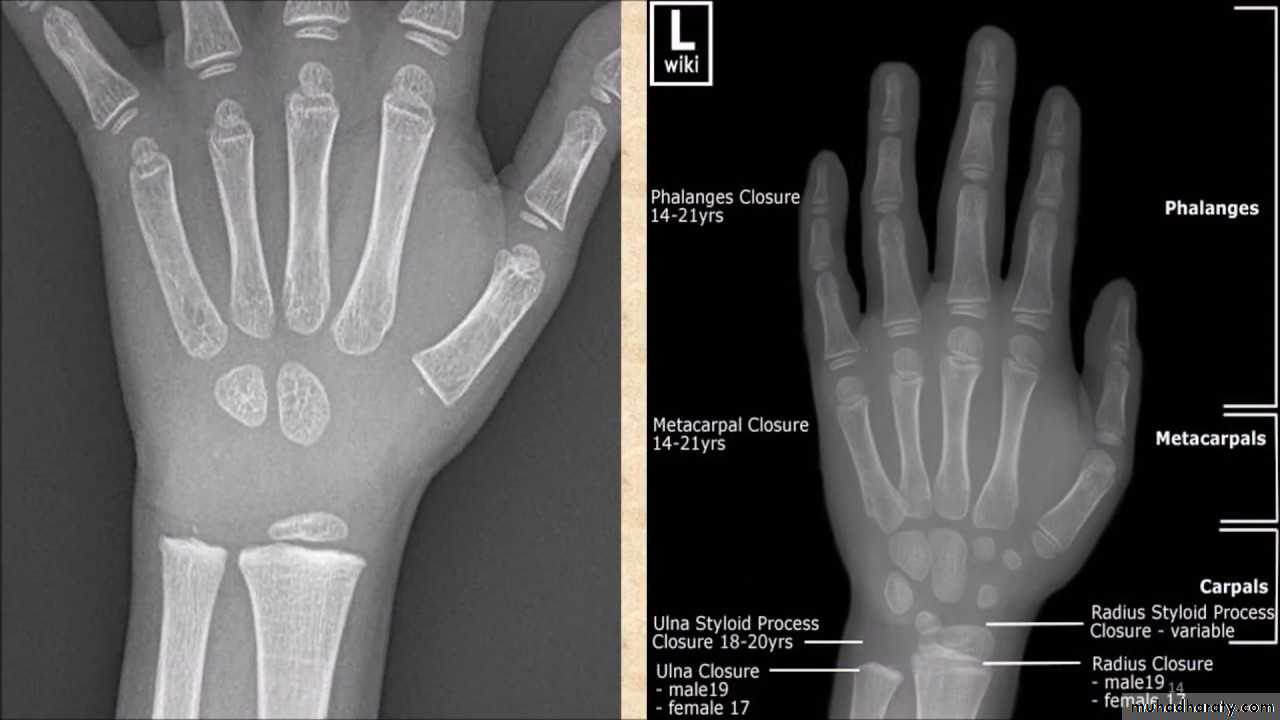

• عمليا يتم تصوير الرسغ والمرفق والكتف لمن يبدوا ظاهرا دون سن العشرين عاما من العمر. ويصور الحرقف لمن بدا في اواسط العقد الثالث من العمر او اقل, والنهاية الانسية للترقوة والتحام القص بالرهابة لمن تجاوز ذلك.

55• معدل ظهور والتحام المراكز التعظمية تبعا للعمر:

• 1) عند الولادة يظهر المركز التعظمي للنهاية السفلى للفخذ والمركز التعظمي لرأس عظم العضد.

• 2) في السنة الاولى( نهاية الشهر الثالث) يظهر (متع) للعظم الرؤيسي والشصي

• وفي الشهر السابع يظهر متع للنهاية السفلى للكعبرة, وفي الشهر العاشر يظهر

• متع للعظم المثلث من عظام الرسغ.

• 2) السنة الثانية يظهر المركز التعظمي للعظم الهلالي الرسغي.

• 3) في نهاية السنة الرابعة يظهر متع لرأس الكعبرة.

• 4) وفي بداية السنة الخامسة يظهر متع للعظم المربع المنحرف وفي نهاية السنة االخامسة يظهر المركز التعظمي لعظمي شبه المنحرف والزورقي الرسغيين.

• 5) في سن السادسة يظهر متع للقمة الانسية لعظم العضد والنهاية السفلية لعظم الزند.

6) في السنة الثامنة ونصف يظهر متع لبكرة العضد.

7) في نهاية السنة التاسعة يظهر متع للنتوء المرفقي لعظم الزند والعظم الحمصي.

8) في نهاية السنة العاشرة يظهر متع اللقمة الوحشية للعضد.

معدل التحام مراكز التعظم:

1) في سن 13-14 سنة تلتحم البكرة بعمد العضد.

2) في سن 14-15 يلتحم راس الكعبرة بالعمد والنتوء المرفقي بالزند.

3) في سن 16-17 سنة تلتحم اللقمة الانسية بعمد العضد.

574) في سن 17-18 تلتحم النهايتان السفليتان للكعبر والزند كل مع عمده.

5) في سن 18-19 يلتحم راس العضد بعمده.

6) وفي سن 25 سنة يلتحم عرف الحرقف بالحرقف والنهاية الانسية للترقوة بالترقوة.